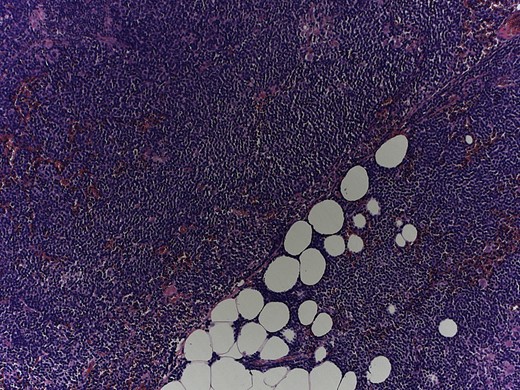

In the pathological assessment the appendix measured 10 and 4.5 cm in diameter. Histopathology revealed an infiltrating non-Hodgkin lymphoma, blastoid B-cell-type, a mantle cell lymphoma. The immunohistochemical pattern was positive for CD20, CD5, Cyclin D1, bcl-6 (that fits for blastoid type), negative for CD3, CD23 and CD10. MIB-1 was up to 75% (Figs 4 and 5).

Magnification 10×, hematoxylin and eosin staining shows a monomorphic lymphoid population with a diffuse growth pattern.